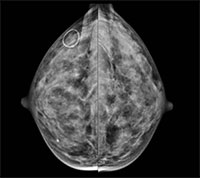

Prior research has shown an association between breast density and breast cancer. In addition, cancers in dense breast tissue are more difficult to see on mammograms. As a result, some women with dense breasts are advised to get supplementary screening with ultrasound or MRI. Some U.S. states have enacted legislation mandating breast density reporting to women undergoing mammography.

Two radiologists read the mammograms independently and determined breast density according to standard criteria. The researchers compared data between patients in the low-density breast tissue group and the high-density group.

The majority of screened woman had low breast density. Of the 230 detected breast cancers, almost half were from the group with the lowest ranked breast density, while slightly less than 3 percent came from women in the highest breast density category.

When the researchers matched the women who had a detected cancer with control participants of the same age and from the same locales who did not have cancer, they found no significant difference in mammographic density. Women with low mammographic density made up 83 percent of the patients in the breast cancer group, compared with 89 percent in the control group, while high mammographic density was found in 17 percent of the breast cancer patients and 11 percent of women in the control group.